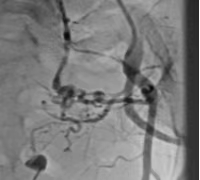

患者,女,54岁,主因“腹腔转移性癌2年,持续性血尿2周”收住,此次入院前2周患者无明显诱出现肉眼血尿及尿中血凝块伴乏力,给予止血治疗后效果欠佳,患者出血量逐渐增多。我科于入院后急诊行“左侧髂内动脉造影”可见:髂内动脉发出三支分支血管供血膀胱,血管迂曲。引入微导管,依次超选三支血管,在透视监视下缓慢注入PVA-0600栓塞微球,栓塞后再次造影可见血流速度较慢、造影剂滞留。撤出微导管,延导丝跟进导管,进入右侧髂内动脉,造影可见:分支血管丰富,血管迂曲,但未见明确膀胱供血血管。经介入栓塞后患者当天晚上膀胱冲洗液由鲜红色转为淡红色,次日清晨冲洗液彻底转为无色。

栓塞前造影 栓塞后造影